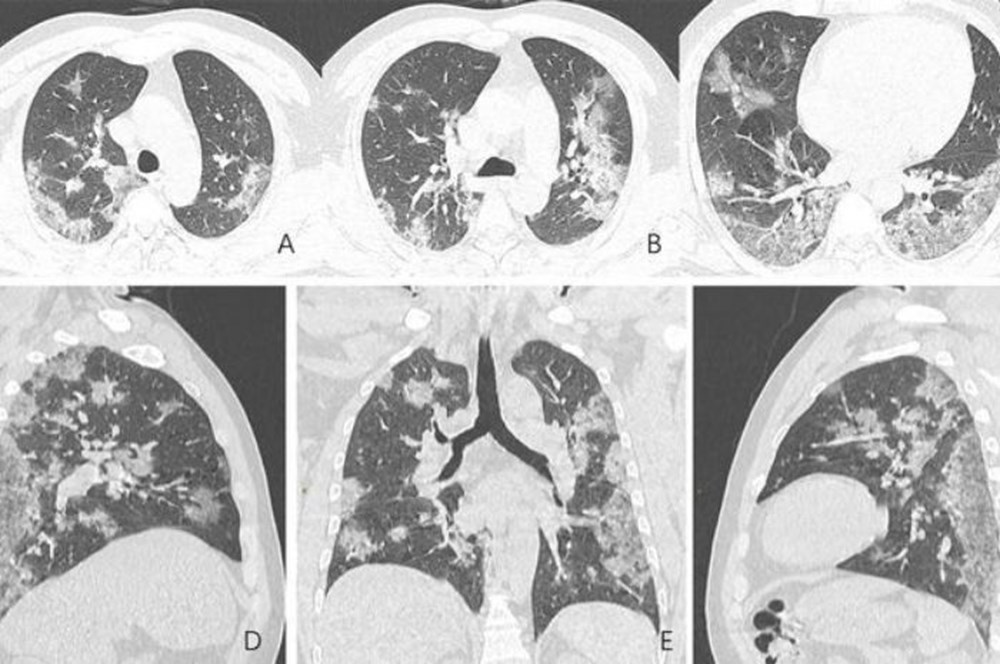

X-ray ışını taramalarında virüsün etkileği yerler beyaz olarak görülüyor. Uzmanlar, hastada virüsün akciğerlerdeki hava keseciklerini kısmen doldurduğunu ve akciğer nodüllerine sebep olduğunu belirtti.

Diğer taraftan aynı tip anormalliklerin SARS (Şiddetli Akut Solunum Sendromu) ve MERS (Ortadoğu Solunum Sendromu) vakalarında da görüldüğünü söylediler.

Ayrıca, A görüntüsüyle F görüntüsü karşılaştırıldığında, akciğer uzuvlarında bulunan sıvının, zaman içinde belirgin bir şekilde koronavirüs nedeniyle arttığı görülebiliyor.

Röntgenleri paylaşılan adamın yaklaşık iki hafta boyunca ateş ve öksürük belirtileri göstermesinin ardından 25 Aralık 2019'da hastaneye kaldırıldığı bir hafta sonra ise hayatını kaybettiği açıklandı.